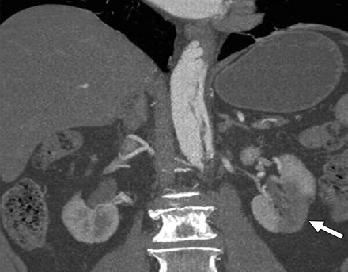

Hình 17: (a) Biến chứng của bóc tách động mạch chủ ngực. Trên Hình axial ngang qua bụng thực hiện ở một bệnh nhân khác, vành bóc tách lòng giả không bắt thuốc chạy lan vào động mạch thận trái và không bắt quang thận trái, một dấu hiệu phù hợp với thiếu máu-nhồi máu nặng. Động mạch thận phải được cấp máu bởi lòng thật và thấy bắt quang bình thường. Ngược lại, trong tắc động, vành lớp áo trong sa xuống qua nguyên ủy động mạch thận, hoạt động như bức màng và bao phủ lỗ động mạch thận. (b) Hình coronal qua bụng cho thấy động mạch thận trái không bắt quang (mũi tên) phù hợp với thiếu máu-nhồi máu thận. Vành bóc tách được nhìn thấy ở động mạch chủ xuống.

Hình 18: Biến chứng của bóc tách động mạch chủ ngực. Hình coronal qua bụng ở một bệnh nhân thứ ba cho thấy vùng giới hạn rõ đậm độ thấp (giảm tưới máu) ở thận trái (mũi tên), một dấu hiệu phù hợp với nhồi máu thận cấp. Vành bóc tách được ghi nhận ở động mạch chủ xuống.